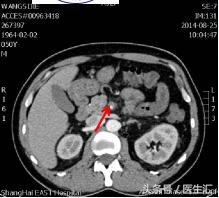

第7天凌晨2:00夜班医生查体全腹部平软,但是上腹部有一点点轻压痛,无反跳痛,麦氏点无压痛,夜班医师给与654-2解痉处理,但是效果还是不满意。所以做了一个中上腹CT平扫示:肠系膜上动、静脉周围渗出性改变,建议增强扫描。第7天早上10:00做中上腹增强CT示:肠系膜上动脉内低密度影,考虑附壁血栓形成,局部管腔重度狭窄。这个时候这个患者的诊断应该来说已经很明确了。于是请了相关科室的医生进行会诊,决定进行经皮选择性肠系膜动脉造影+肠系膜动脉溶栓术。患者溶栓导管行脉冲式注射尿激酶溶栓,患者术后24h出现便血4次,200ml/次。